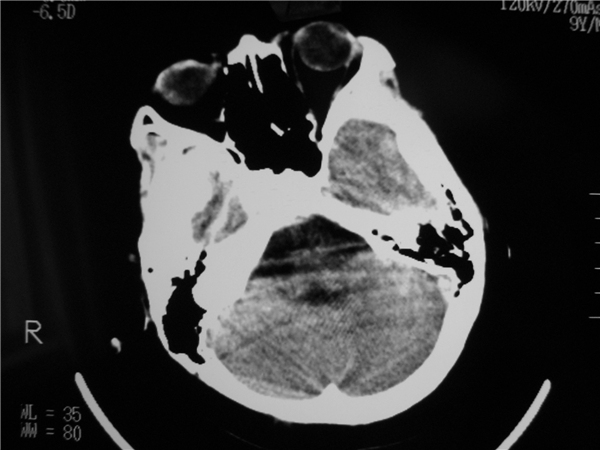

以下是引用余辉在2009-9-2 8:06:00的发言:[br]右侧侧脑室扩大,脑髓质量明显减少,胼胝体区结构不良,脑沟增深。考虑右侧大脑萎缩伴胼胝体发育不良(可能后遗改变(hie史?)),请查病史。第三脑室四脑室扩张,应该有脑积水存在

以下是引用拾荒者在2009-9-2 20:53:00的发言:[br]右侧侧脑室扩大,脑髓质量明显减少,胼胝体区结构不良,脑沟增深。考虑右侧大脑萎缩伴胼胝体发育不良。至于是否合并脑炎,可结合实验室检查或脑脊液检查。